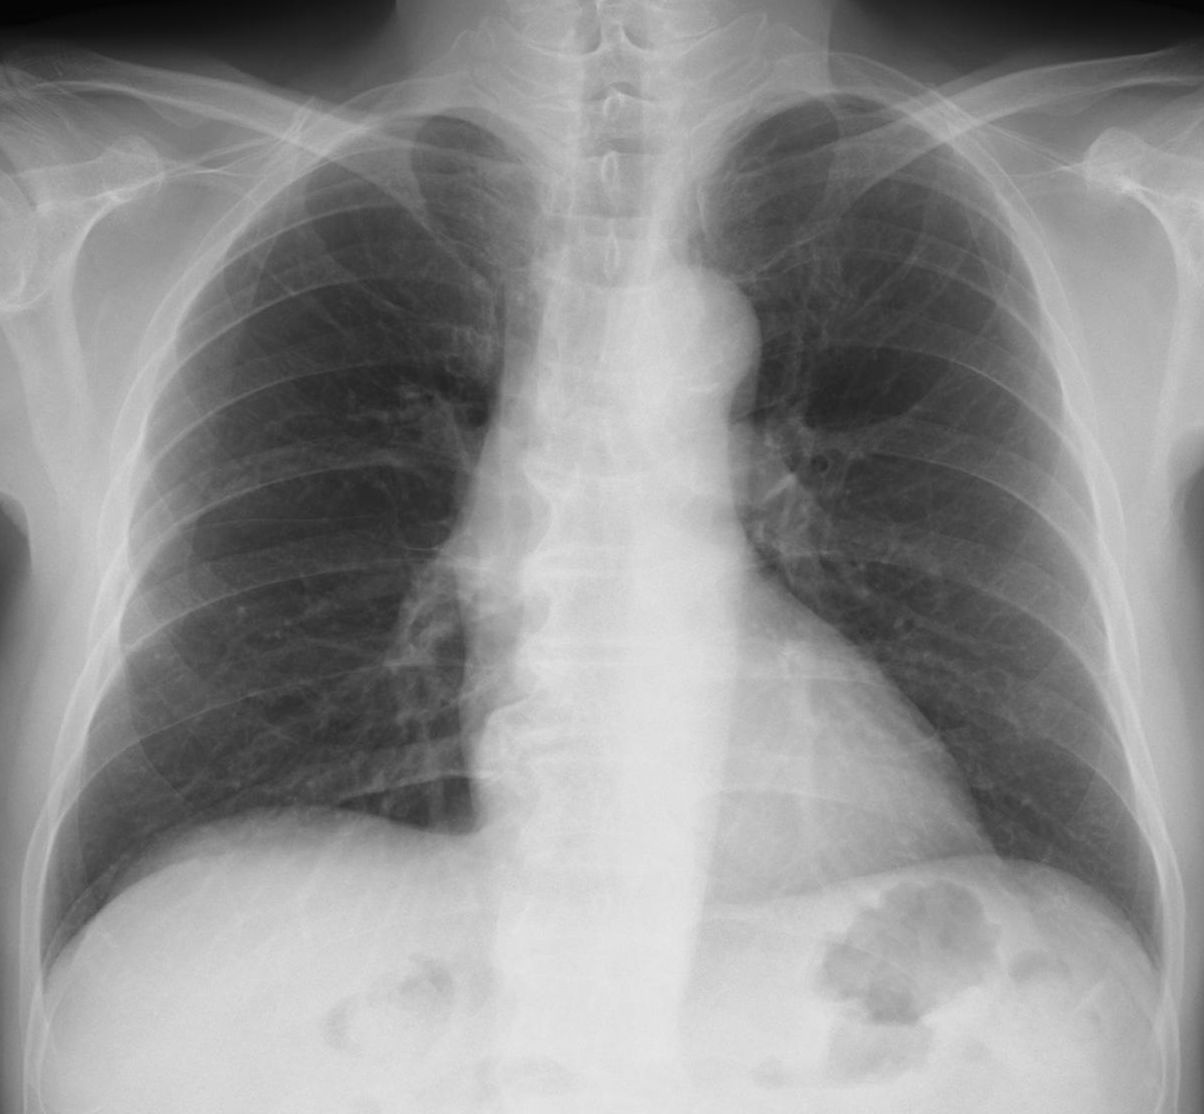

[注意] 心陰影にみえる肺門陰影(右)、シルエットサイン陰性に気づけば肺炎像と理解できる。また、左肺門部陰影は心辺縁が不鮮明(シルエットサイン陽性)で同部にも浸潤影があることが推定できる。 肺門部の浸潤影はいつも慎重に判断する必要がある。下写真の左肺門部の心陰影ははっきりせず(左上挿入写真は治癒時)判断に迷うがシルエット陽性と判断すればS6もしくはS3の肺炎が推定可能になる。下の写真はS6の浸潤影が想定される。 [肺門の陰影]

左は肺門の変化からマイコプラズマ肺炎と診断、オゼックス投与にて解熱しないため3日後に確認したところ浸潤影が拡大していた。 [心陰影の把握]